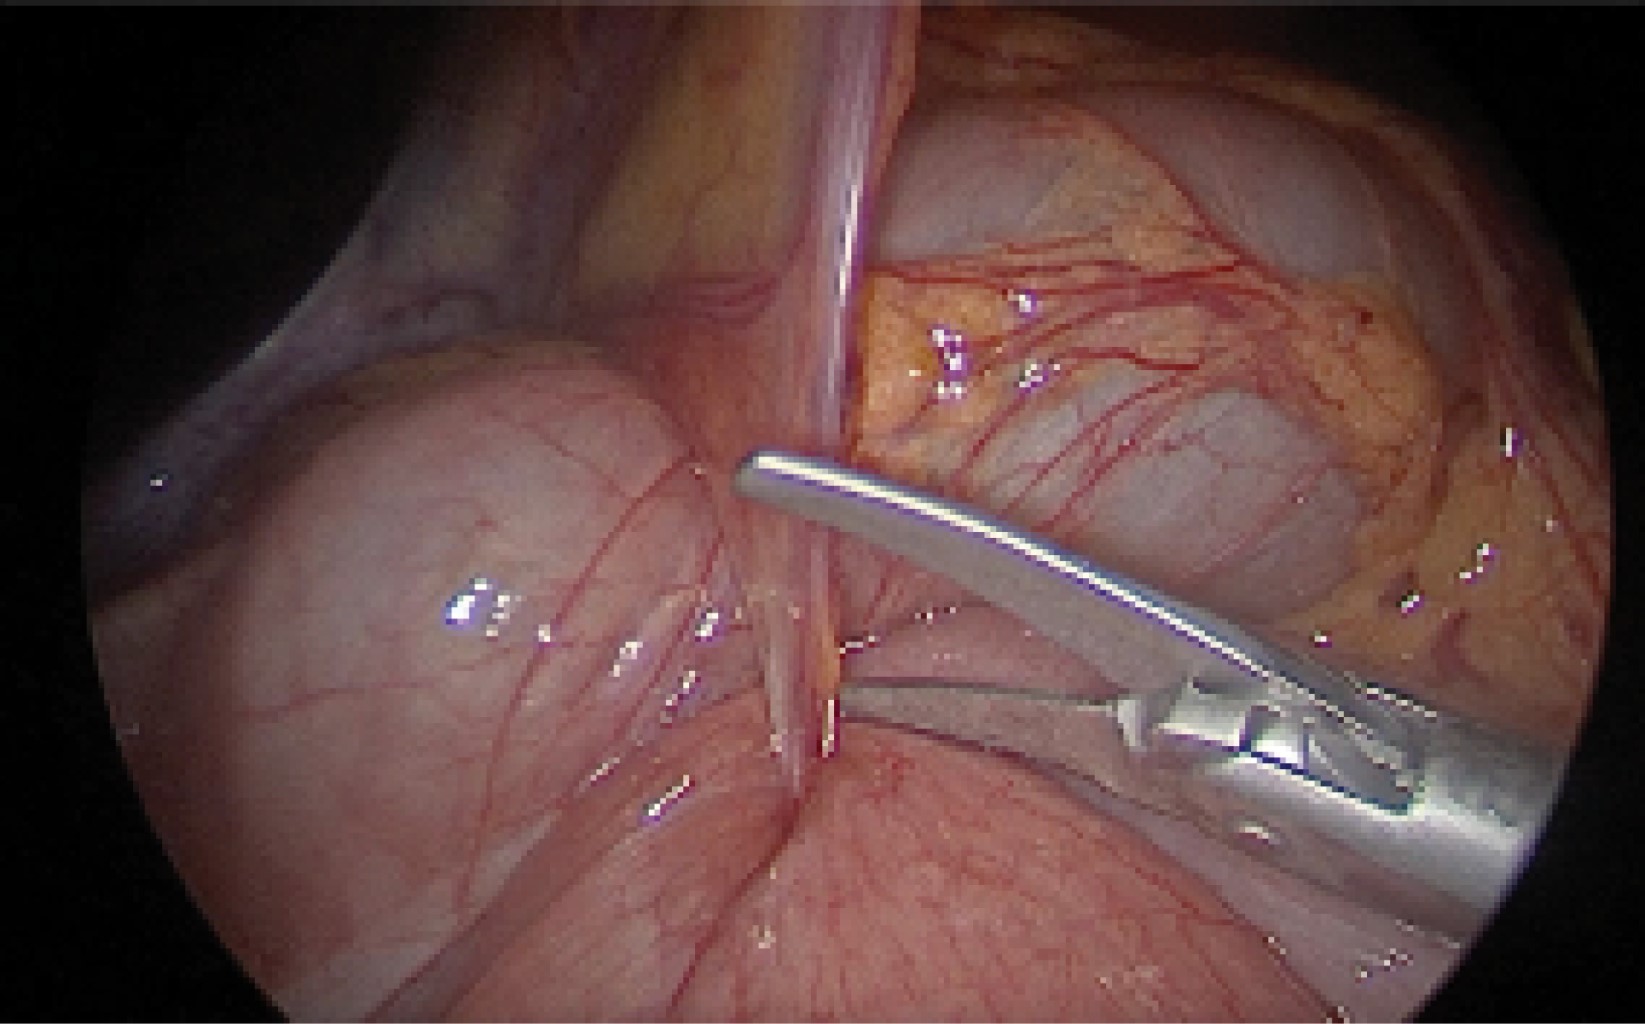

Se indicó el manejo quirúrgico con base en laparoscopía diagnóstica. Se colocaron puertos sin incidentes, no se observó líquido libre ni distensión de asas. Se identificó colon transverso e intestino delgado (yeyuno) atravesando un orificio en la unión de los ligamentos falciforme y el redondo del hígado (Figuras 2 y 3). Ese segmento intestinal no presentaba alteraciones de perfusión, el yeyuno mostraba leve aumento en la vascularidad. Ninguna de las dos estructuras se encontraban fijas al ligamento. Se aplicó corte frío en el borde posterior del cordón y se liberaron ambas asas intestinales, las cuales presentaron peristalsis espontánea. Se efectuó la revisión del resto de la cavidad sin encontrar otras claves y se realizó el cierre de puertos de forma usual. Se reportó un sangrado posoperatorio de 5 mL y un tiempo quirúrgico de una hora con 30 minutos.

Figura 2